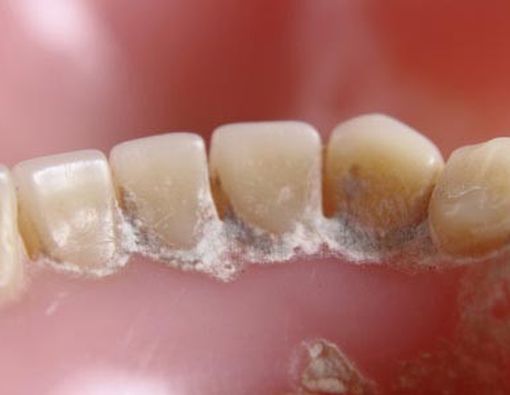

Banyak orang yang mengabaikan keberadaan karang gigi (dental calculus) di dalam mulut, karena dianggap sebagai sesuatu yang tidak membahayakan kesehatan tubuh. Padahal, karang gigi merupakan faktor utama terjadinya peradangan jaringan pendukung gigi (jaringan periodontal), yang disebut periodontitis.

Permukaan karang gigi yang kasar dan berpori menjadi tempat yang ideal bagi pertumbuhan bakteri dalam rongga mulut dan bertindak sebagai wadah yang menampung bagi komponen produk bakteri yang bersifat toksik bagi jaringan lunak mulut.